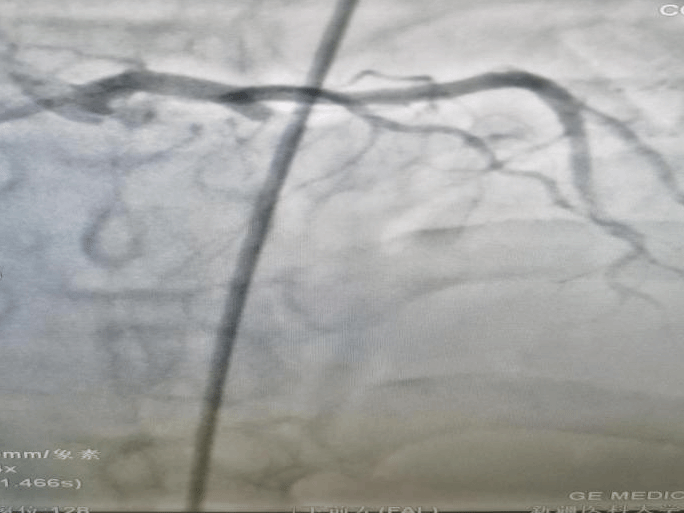

冠状动脉造影证实,患者心脏最重要的血管“前降支”闭塞,在前期准备充分的情况下,从患者转运入院到前降支血管打通,团队仅用时15分钟,为患者赢得了宝贵的“心肌存活时间”。